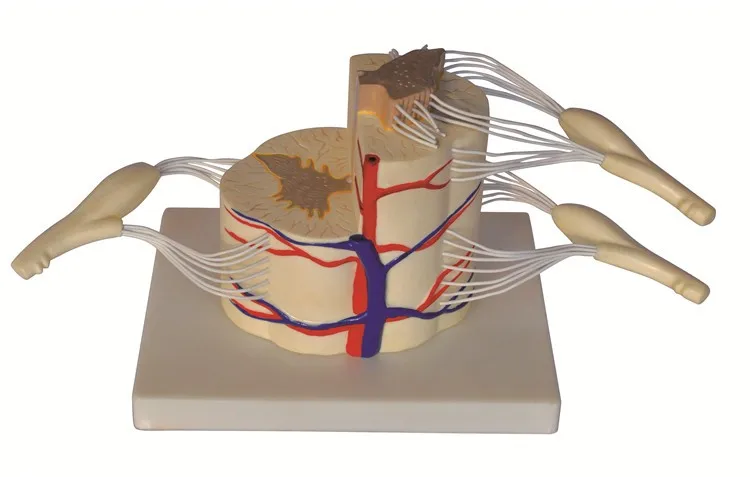

Vertebral Dan Sumsum Tulang Belakang Model Parsial Buy Model Anatomi Model Medis Model Pendidikan Product On Alibaba Com

Vertebral Dan Sumsum Tulang Belakang Model Parsial Buy Model Anatomi Model Medis Model Pendidikan Product On Alibaba Com

Vertebral Dan Sumsum Tulang Belakang Model Parsial Buy Model Anatomi Model Medis Model Pendidikan Product On Alibaba Com

Vertebral Dan Sumsum Tulang Belakang Model Parsial Buy Model Anatomi Model Medis Model Pendidikan Product On Alibaba Com